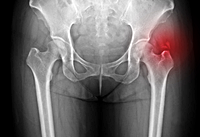

6. 보행 시 절뚝거림

젊은 층에서도 발생하며, 대퇴골두 무혈성 괴사일 가능성이 있습니다. 과음, 고지혈증, 스테로이드 남용 등이 원인이 될 수 있습니다.